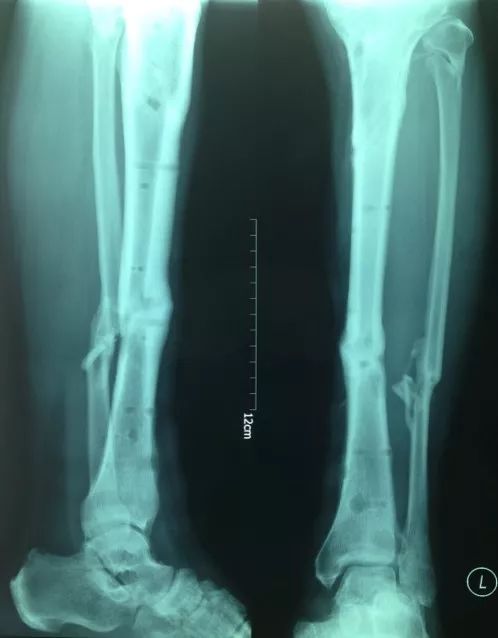

患者,男,56岁,脑外伤及下肢开放伤,急诊手术未使用双氧水,生理盐水冲洗伤口,外固定架固定,伤口游离植皮闭合。骨折及伤口获良好愈合

化繁为简固定法

• 按照多段骨折化繁为简固定方式复位固定近端骨折实现闭合处理。

• 创面新鲜后植游离皮

• 尽快下地走路,生理应力促进骨愈合

• 近端3个月愈合,远端用8个月

• 而后去除外固定架

• 如果使用双氧水会造成骨膜破坏,骨坏死外露,而后骨缺损,需要皮瓣植骨或骨搬运。